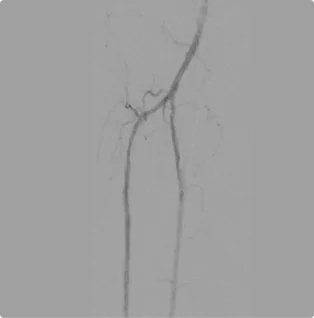

After

After working to clear the blockages from both sides, Dr. Goldstein establishes flow through the two lower branches of the arteries, allowing blood to flow down into the foot.